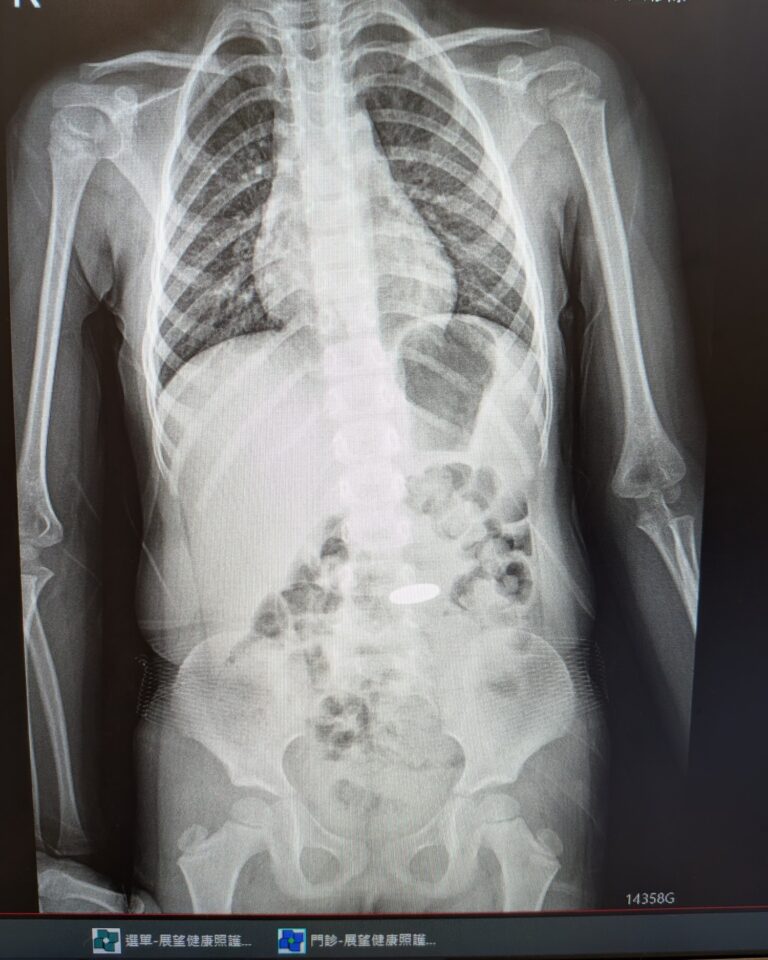

不少有屏息症候群的孩子,同時也有缺鐵。有些孩子在補充鐵劑後,發作頻率會明顯下降,因此若反覆發作,醫師常會評估是否需要抽血檢查。